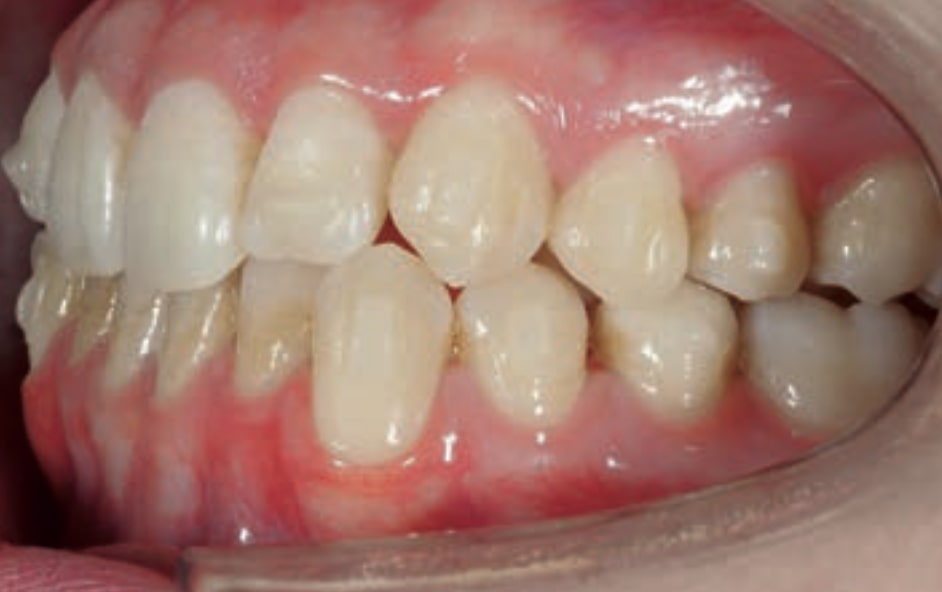

Chief complaint: The patient, a 19-year-old woman, was evaluated to undergo orthodontic treatment using the Angel Aligner Pro system. She presents with a skeletal Class III, mesofacial, with a dental Class III malocclusion and a 2 mm deviation of the lower midline to the left. Teeth 33 and 43 are out of the arch and cortical bone, with a crossbite issue on tooth 33. Fortunately, no functional issues affecting swallowing or breathing have been detected. The patient’s motivation for starting treatment was a general review of her dental and aesthetic health. The soft tissue analysis reveals mandibular protrusion that influences her facial profile. This diagnosis highlights the need for a comprehensive approach to address dental and skeletal misalignments, improving both the patient’s functionality and facial aesthetics.

- Dental Class III, 2 mm deviation of the lower midline to the left. 33 and 43 out of the arch and the cortical bone.

- Crossbite of 33.